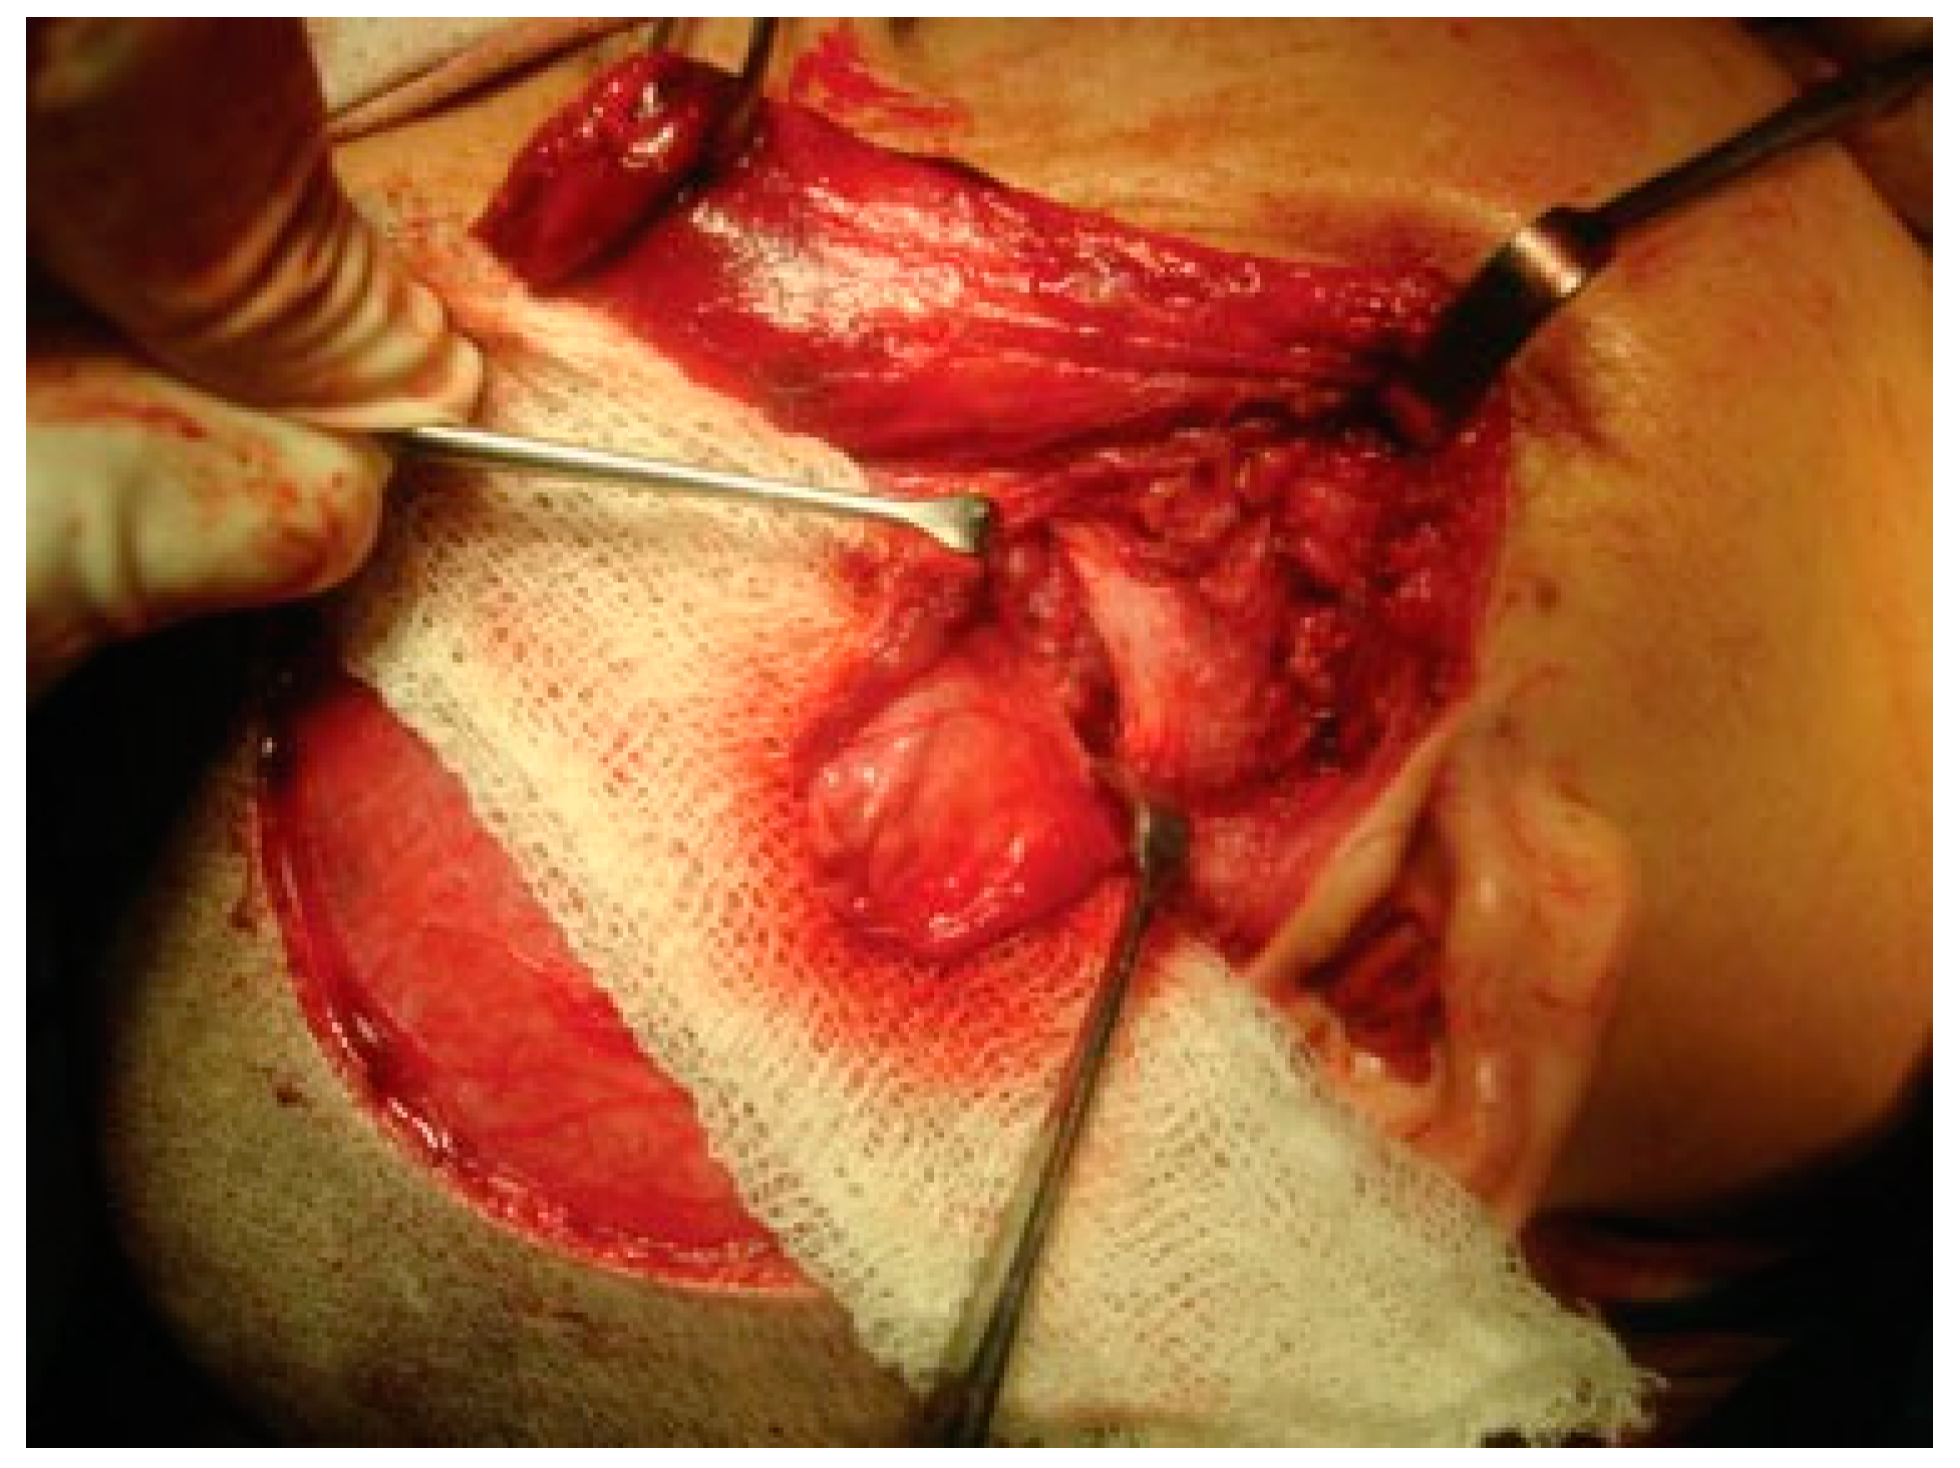

Reconstruction of the TMJ after release of ankylosis assumes paramount importance in terms of restoration of facial form and function. The goals of treatment in all the patients were the release of ankylotic mass, restoration of normal jaw form and function, symmetric growth of the mandible in children, and most importantly the prevention of reankylosis. All interpositional arthroplasties are to some extent the autogenous reconstruction of the morbid ankylotic TMJ after resection of the ankylotic mass. Merriam Webster Dictionary defines reconstruction as the act or process of building something that was damaged or destroyed again. Reconstructive surgery refers to a procedure whose goal is intended to restore form and function in structures deformed or damaged by disease, congenital anomaly, tumor, trauma, or infection (Farlex Partner Medical Dictionary Farlex 2012). The treatment of TMJ ankylosis is individualized based on the severity of ankylosis, age of the patient, and other patient factors. We have outlined our experience following Kaban’s protocol in the management of TMJ ankylosis. It is of paramount importance to obtain passive and maximal mouth opening using this protocol in terms of adequate resection and ipsilateral or contralateral coronoidectomy whenever required followed by aggressive physiotherapy (Figure 5 and Figure 6). Physiotherapy was started on third day postoperatively using Heister mouth gag five times a day during the hospital stay of the patient. This device was purchased by the patient after discharge from the hospital for physiotherapy at home. The MIMO and excursive movements were recorded at various follow-ups for all the patients. No intermaxillary fixation/elastics were applied to any of the patients in the series.

Figure 5. Intraoperative passive mouth opening.